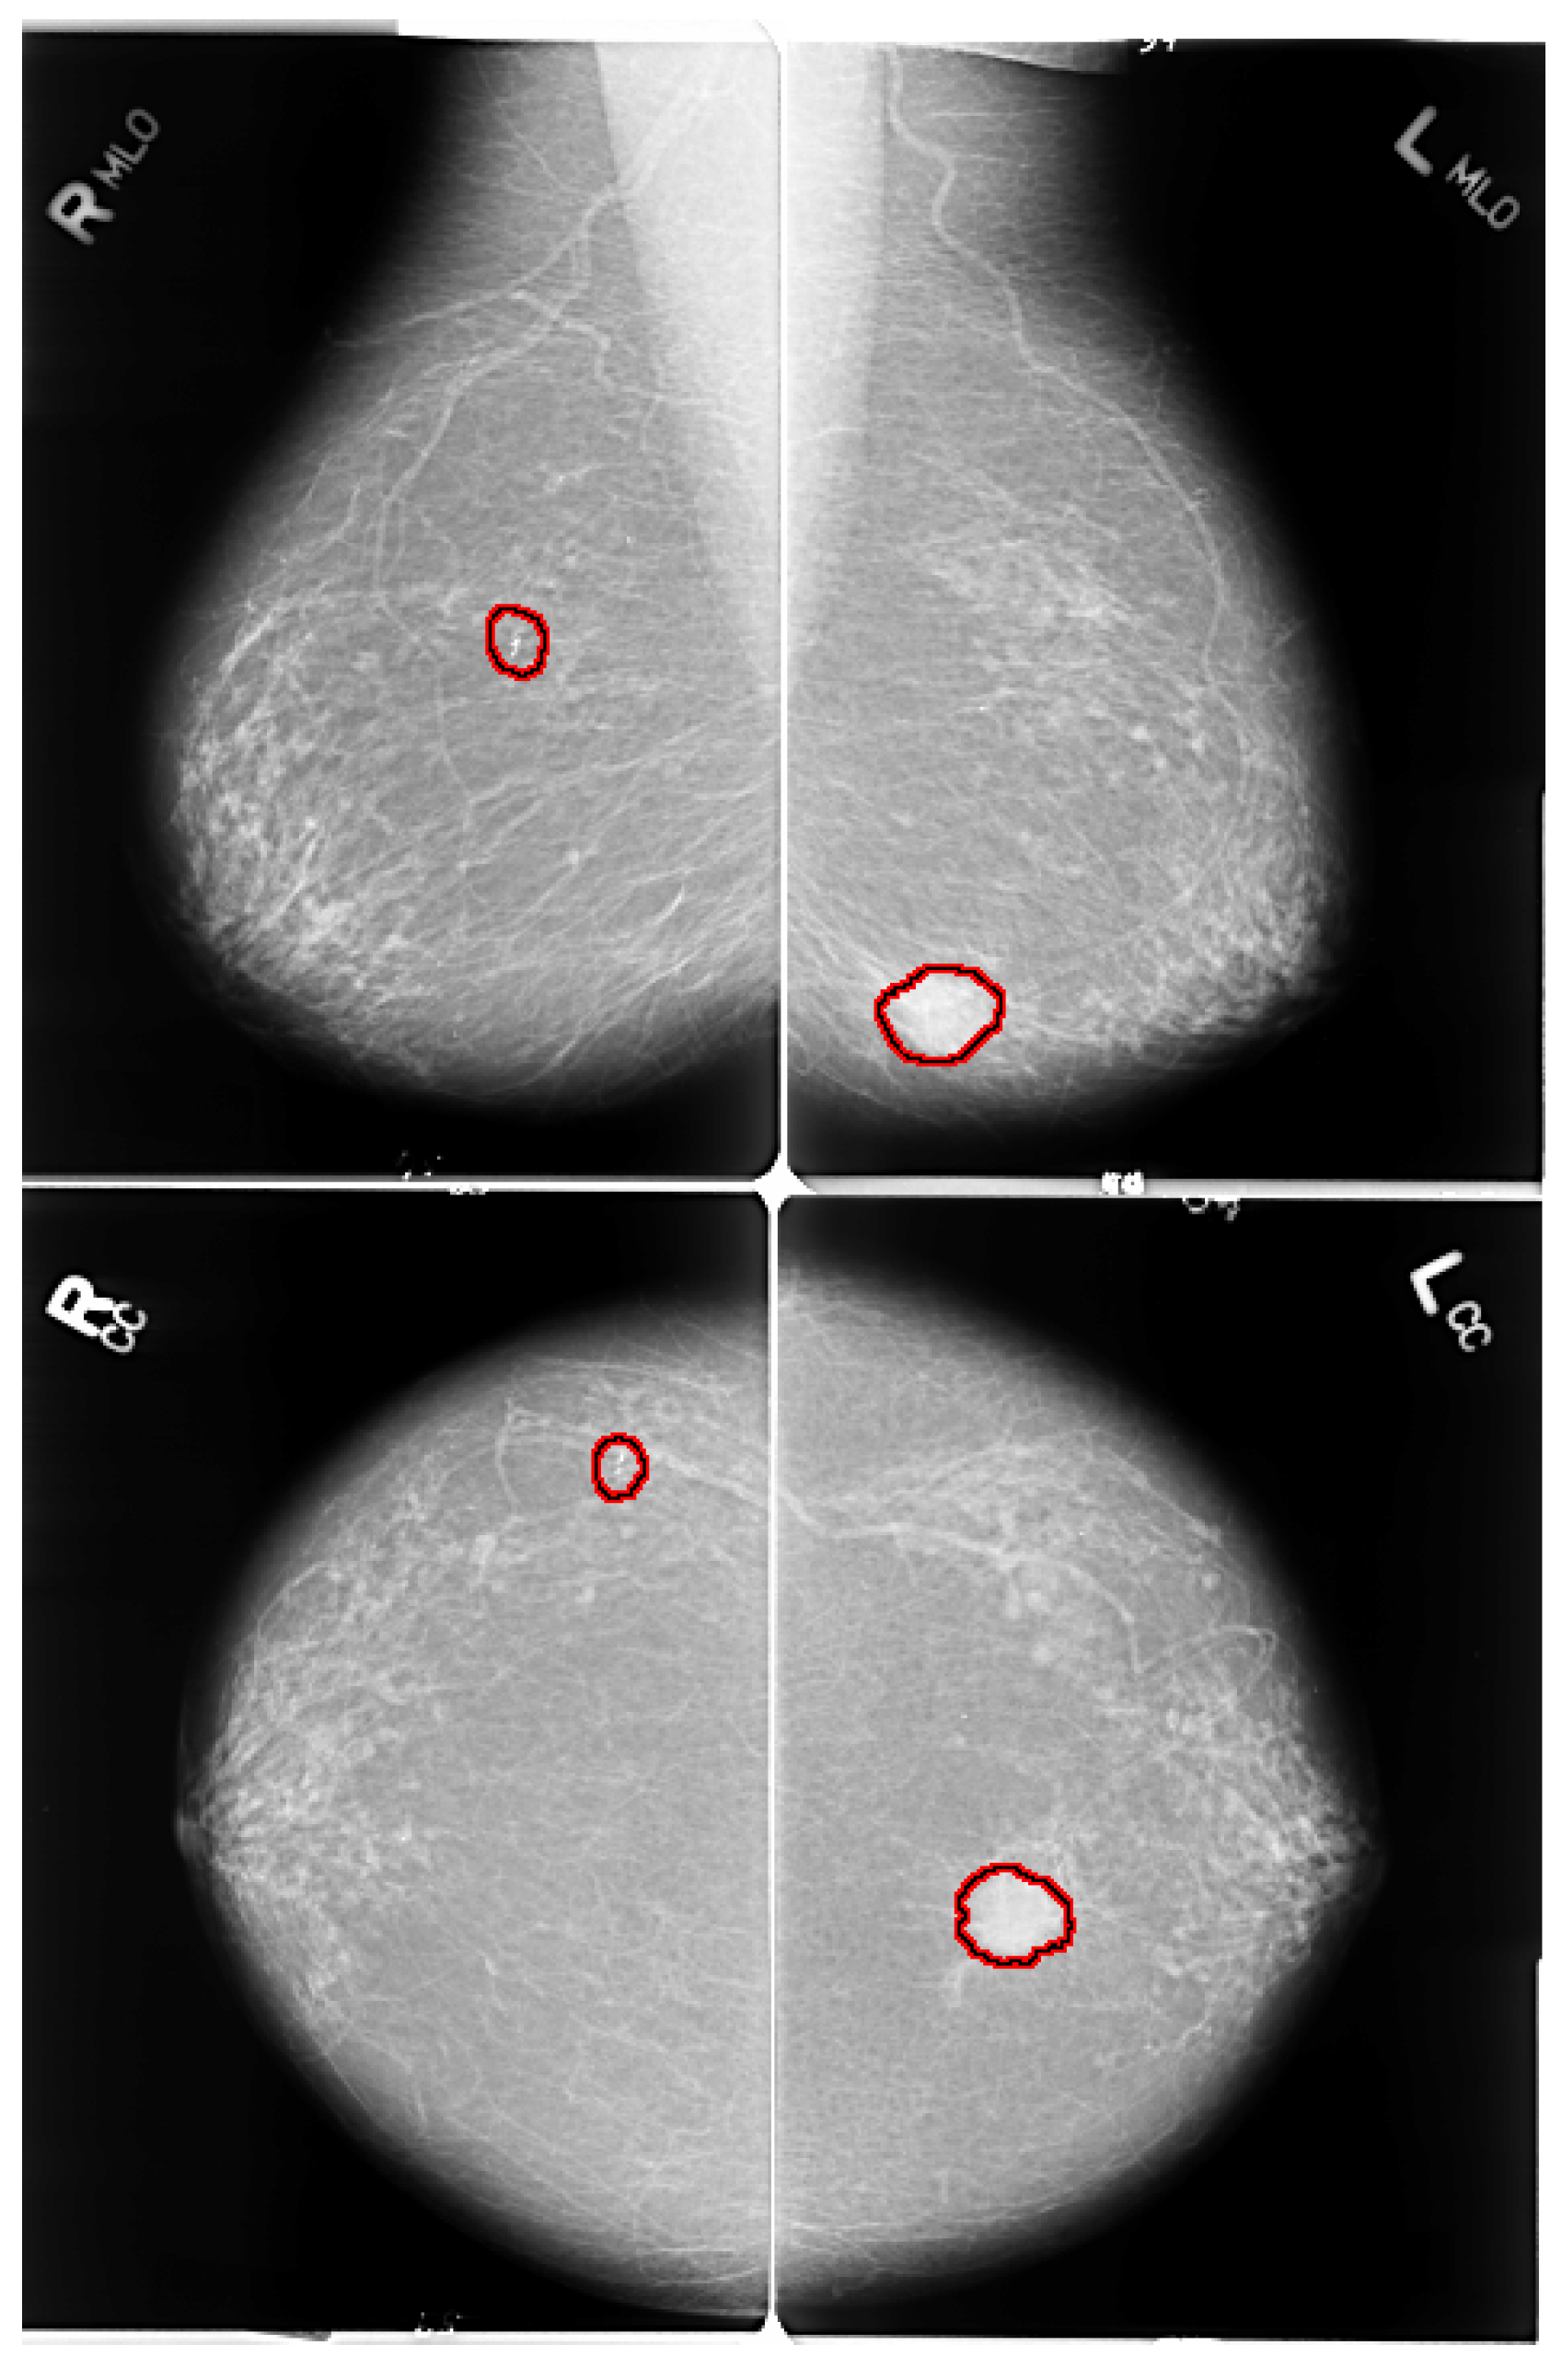

2.1. Breast Positioning and Projection View

2.2. Various Forms of Breast Abnormalities

- Mass: A mass is a 3D lesion that can be seen in various projections. Morphological features, such as shape, margin and density, are used for mass characterisation. The shape can be round, oval or irregular. The margin can be not well defined, microlobulated, speculated, indistinct or circumscribed. Figure 4 shows the graphical representation of these morphological features (shape and margin) of a mass along with their subcategories. When superimposed breast tissues hide margins, that is called obscured or partially obscured. Microlobulated infers a suspicious finding. Spiculated margin with radiating lines is also a suspicious finding. Indistinct, also termed as ill-defined, is a suspicious finding too. Circumscribed is a well-defined mass that is a benign finding. Density can be high, low or fat-containing. The density of a mass is related to the expected attenuation of an equal volume of a fibroglandular tissue [6,20]. High density is associated with malignancy.